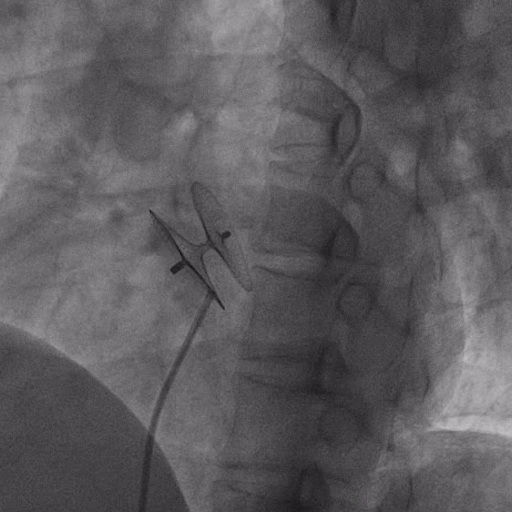

在獲得患者同意后,1月12日,尚福軍主任為患者進(jìn)行了PFO封堵術(shù)。術(shù)中造影可見封堵器殘余漏,尚福軍主任用精湛的技藝,順利通過(guò)封堵器殘余漏裂縫,將右心導(dǎo)管從右房送入左房,且順利到達(dá)肺靜脈;遂行卵圓孔未閉封堵術(shù)后殘余漏再次封堵;且完美釋放PFO封堵器,可見兩封堵器呈“馬蹄蓮”狀,再次術(shù)中造影未見殘余漏。

術(shù)后,小鞏生命體征平穩(wěn)。相關(guān)檢查顯示正常,且術(shù)后完善心臟彩超及發(fā)泡試驗(yàn),可見封堵器位置良好,未見右向左分流,發(fā)泡試驗(yàn)陰性。